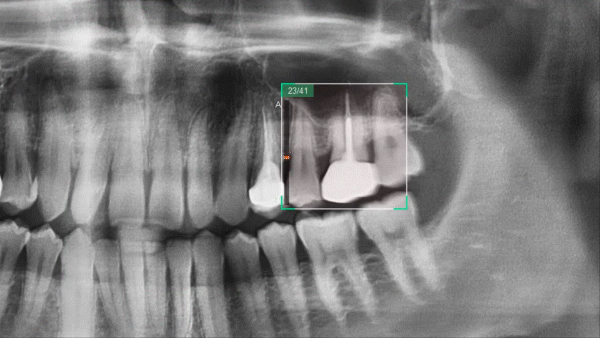

Новый шаг в развитии панорамной визуализации с Insight Pan

Компьютерный томограф Green Smart от Vatech может снимать многослойное панорамное изображение, называемое Insight Pan, которое обеспечивает визуализацию в глубину панорамы. Поскольку у каждого пациента форма зубных рядов и наклон зубов могут отличаться, традиционные панорамные изображения могут иногда пропускать важные детали, которые оказываются за пределами единственного фокального слоя. Функция Insight Pan служит для получения многослойных панорамных изображений, гарантирующих возможность наблюдать необходимую анатомию на нужной глубине.

Insight Navi

Insight Navi в программе EzDent-i — это специальная функция для аппарата Green Smart. Она позволяет получить информацию о внутренних структурах послойно перемещаясь на панорамном снимке вперед-назад. Insight Navi предоставляет дополнительные срезы выбранной зоны интереса. Исследуя дополнительные срезы, вы можете обнаружить изображения мезиальных, дистальных и даже небных корней.